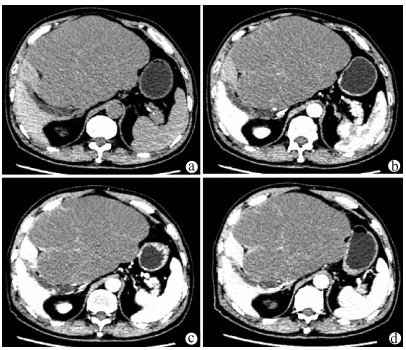

A case of huge intrahepatic biliary papillomatosis